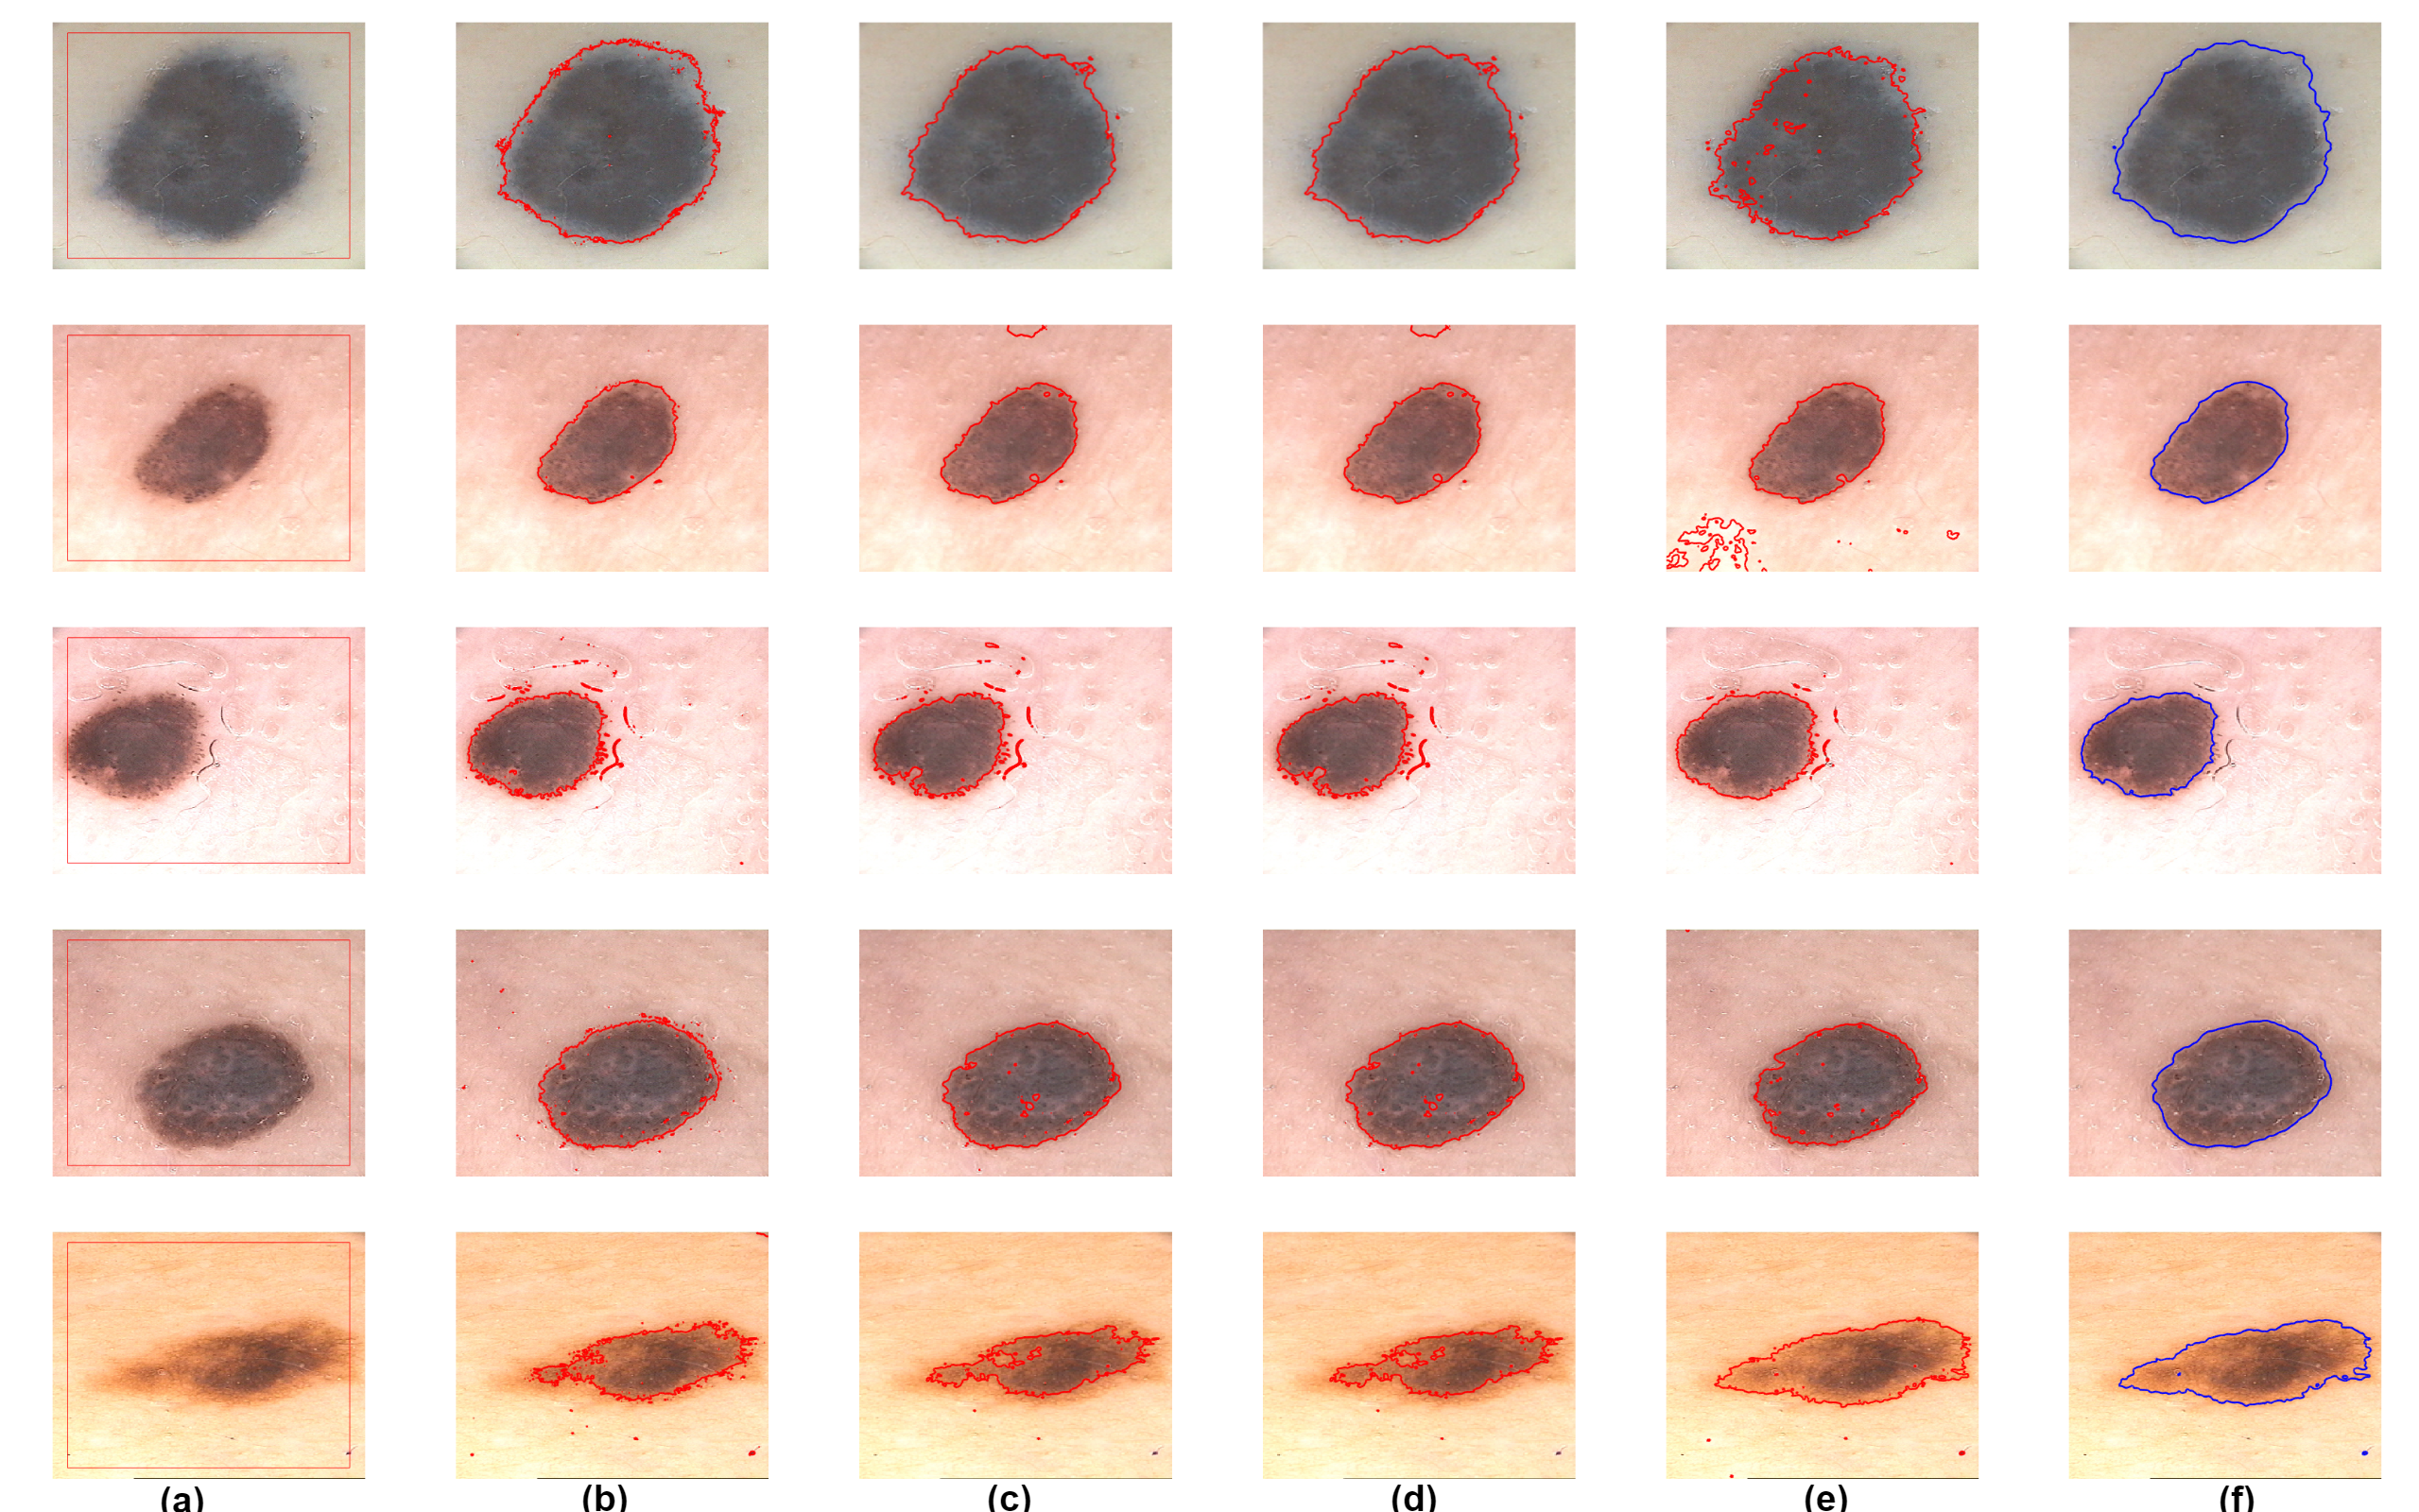

The increasing incidences of melanoma, a type of skin cancer, have recently promoted the development of computer-aided diagnosis (CAD) systems for the segmentation of dermoscopic images. Because is a dermoscopic image database, we also tested our model on a dataset of dermoscopic images [48]. Fig. (13) shows the experiments conducted to segment melanoma from the skin. Here, the first column shows the initial contour, and the second to the last columns are the results of the CV, LBF, LIF, SDREL, and proposed models, respectively. All previous model results on the images are acceptable, although in some images these models show false contours and noise, whereas the proposed model clearly segments the melanoma from the skin.

These quantitative comparisons of all models were conducted to measure the Dice Index, Jaccard Index, and BF score over the [48] dataset of dermoscopic images. Three evaluation measurements are calculated for each image shown in (13) against each model. Fig. (14) shows the mean of these evaluation measurements in a graphical context. All image segmentation evaluation analysis techniques prove that the proposed saliency driven active contour model achieves the highest Dice Index, Jaccard Index, and contour matching score (BFscore) in comparison to the previous related models.